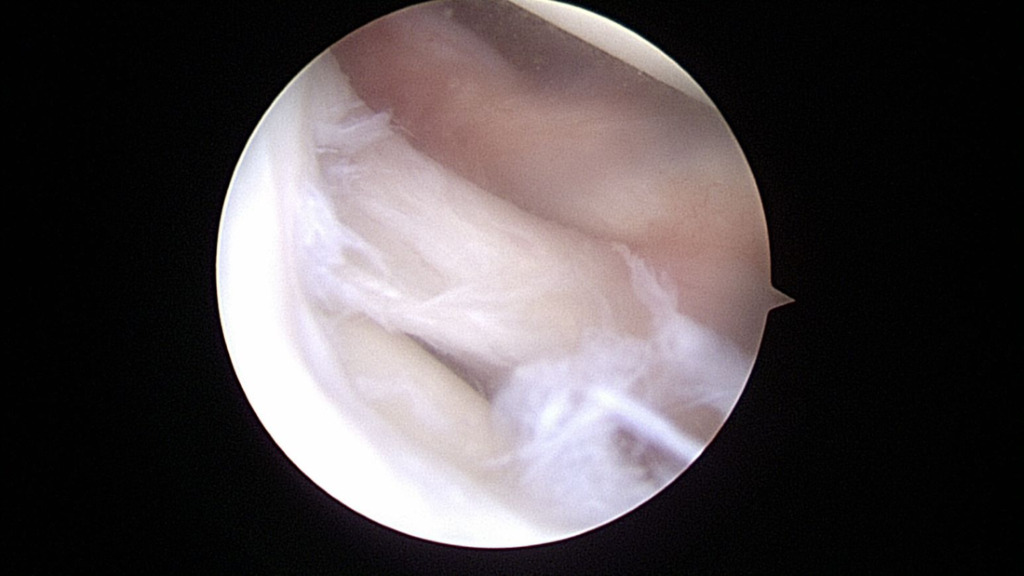

The ACL and PCL were intact. The lateral compartment revealed a lateral meniscus tear with the tissue displaced centrally into the notch, impinging on the ACL (Figure 5).